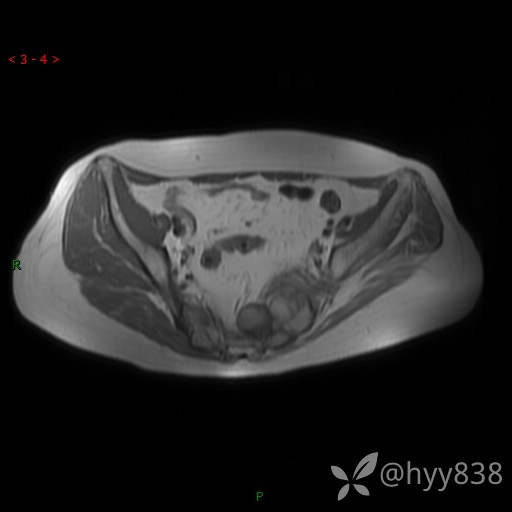

骨盆MRI平扫(T1WI+T2WI+DWI)(外院CT,不能上传)